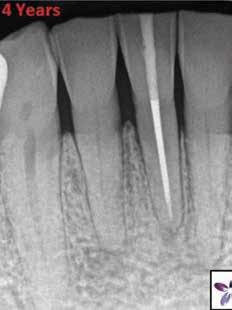

5. a–l. ábrák: Az incisális élen keresztül kialakított hozzáférés lehetővé teszi a pericervikális dentin megőrzését. Kalcifikáció esetén CBCT-felvétel készítése hasznosnak bizonyulhat a hozzáférési nyílás tervezése során (a–d) . Minden fog koronai helyreállítása a gyökértömés elkészítésével egyidejűleg történt. A négyéves (e–h) és a kétéves (i–l) kontrollok alkalmával készített röntgenfelvételeken teljes gyógyulás látható. Mindkét fog tünetmentes és funkcióképes volt. (Dr. Viraj Vora esetei)

kialakítása során fennáll a fog labiális irányú perforációjának veszélye, mivel ilyenkor a foganyag elvételét labiális irányú fúrótartással kezdjük. Nemrégiben újragondolták a

sálisabb megközelítéssel javasolták. 21,22 Az új ajánlásban azt javasolják, hogy a frontfogakban történő hozzáférési nyílás kialakítását a cingulumtól távolabb, inkább az incizális él közelében kezdjük meg 19. Ez lehetővé teszi a lehető legtöbb pericervikális dentin megőrzését és kizárólag a legszükségesebb mennyiségű dentin kerül eltávolításra. Emellett ez a kialakítás a cingulumon keresztül történő hozzáféréshez képest egyenesebb hozzáférést biztosít a labiális és a linguális, vagy palatinális csatornákhoz, valamint lehetővé teszi a csatornák hatékonyabb tisztítását. 21 A fogak kopása esetén a hozzáférést az incisális „felszín” közepén alakítjuk ki (3. a-b ábrák) . A frontfogak kezelése során a megfelelő fúró kiválasztása is kiemelkedően fontos szereppel bír. A korábban ajánlott gömbfúrók használata ma már kifejezetten kontraindikáltnak számít. A gömbfúrók használatakor jellemzően egy fordított tölcsér alakú üreg kerül kialakításra. Ezekben az esetekben az üreg egyre szélesebb lesz, ahogy egyre mélyebbre hatolunk a fúrónkkal (2. a-b ábrák) 23 A gömbfúrók helyett olyan fúrók használata javasolt, amellyel elkerülhető lehet a trepanációs kavitás túlzott mértékű kiterjesztése, és amely segítségével a hozzáférési nyílás legszűkebb részét a pericer -

zésére. Ez azért fontos, mert a frontfogak funkcionális megterhelése során – a PCD-nek megfelelően elhelyezkedő területben – jelentős stressz ébred (5. a–l ábrák) 24 Szükség esetén egy CBCT-felvételt is készíthetünk. A 3D-s adatok jelentős mértékben segíthetik a klinikus munkáját a gyökércsatorna koronális vetületének vizualizálásában, és ennek alapján az egyenes vonalú hozzáférés biztosításához szükséges belépési pont meghatározásában (5.